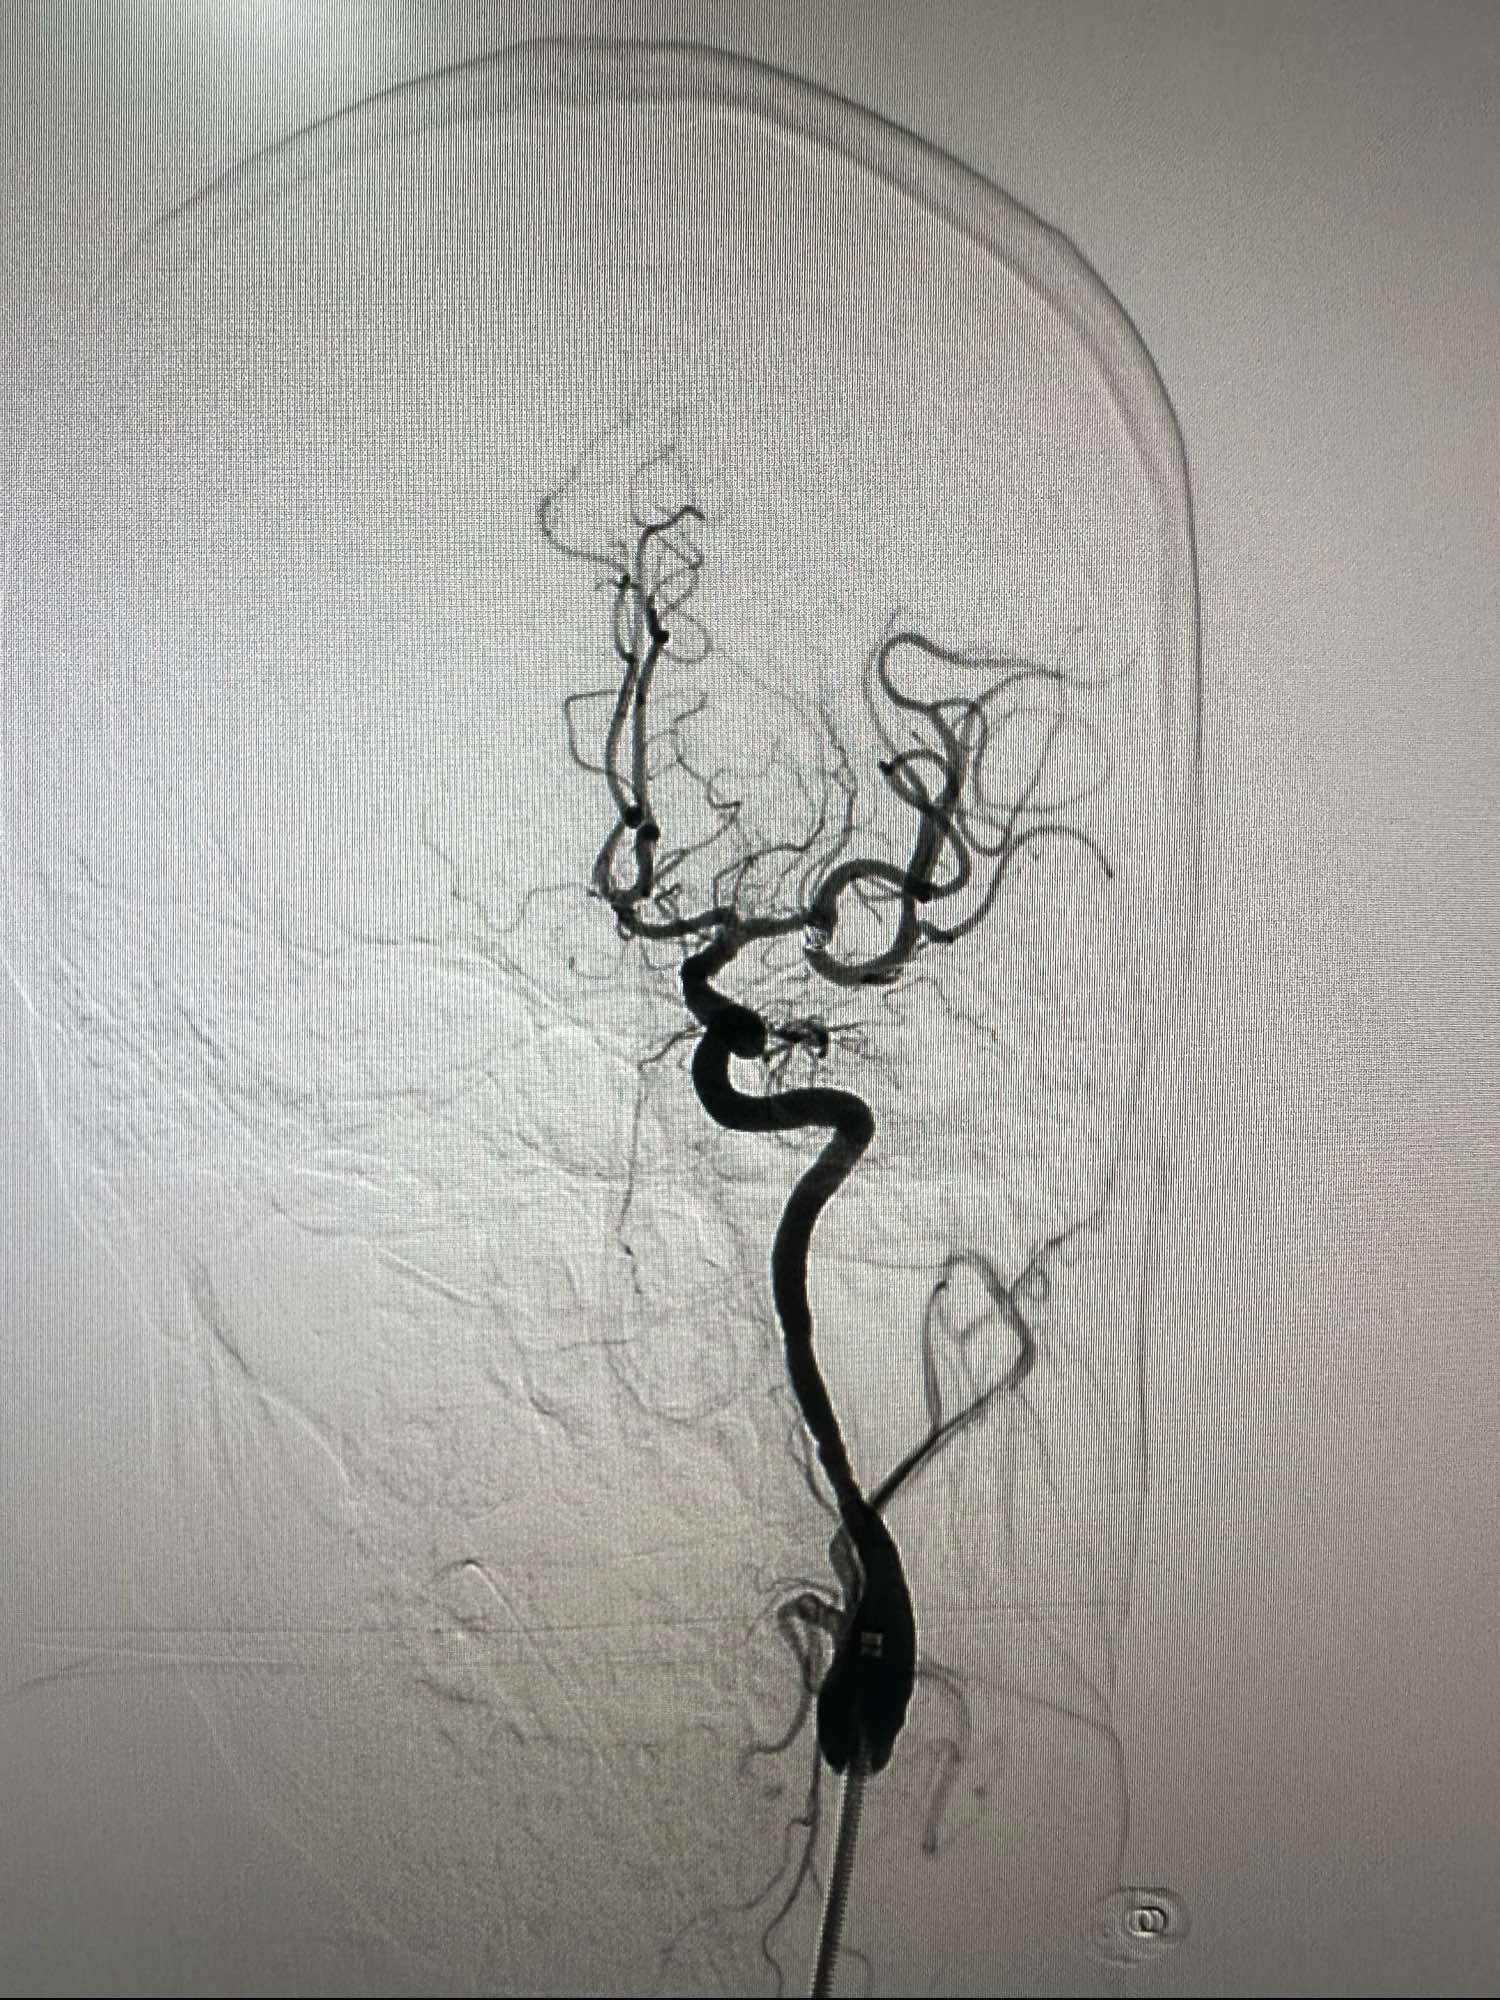

术中发现有血栓,动脉内直接给予新维林8ML,并静脉内持续泵入4ML再次造影见血栓已经完全消失

侧位,术后患者完全清醒,未见特殊异常